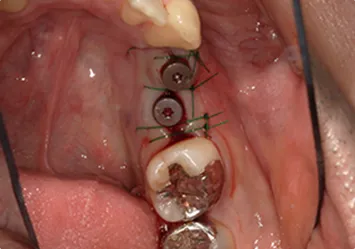

治療前

治療前写真 恵比寿南DENTAL

治療後

治療後写真 恵比寿南DENTAL

施術内容

【40代女性】

右上の前歯が歯根破折となっしまった為抜歯を行い、抜歯と同時にインプラント埋入を行った

治療期間

3ヶ月

リスク

術中の不可抗力によるトラブル(出血など)、術後注意事項を守らないことによる疼痛、感染、上部構造装着後口腔内清掃を怠ったことによるインプラント周囲組織の炎症

副作用

治療後の口腔内清掃、及びメインテナンスを怠ったことによるインプラント周囲粘膜炎またはインプラント周囲炎

費用

インプラント埋入:30万円

ジルコニアオールセラミッククラウン:15万円